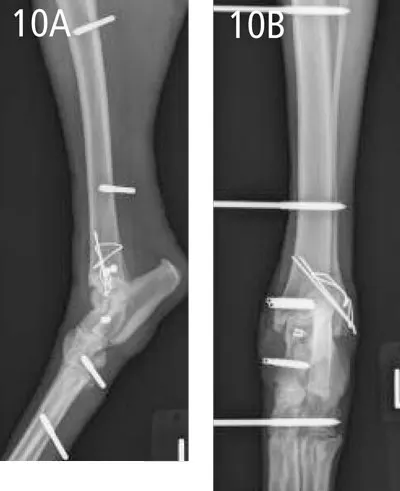

A transarticular, hinged external fixator (Imex Veterinary, www.imex.com) (Figure 9) was placed on the medial aspect of the joint for 8 weeks to provide adjunctive support to the collateral ligaments and to protect the reconstruction while fibrous tissue healing progressed. The hinged fixator was locked for 2 weeks, then progressively adjusted to permit tibiotarsal range of motion over the next 6 weeks. Anatomical reduc-tion and correct implant placement were observed on postoperative radiographs (Figure 10, page 57).